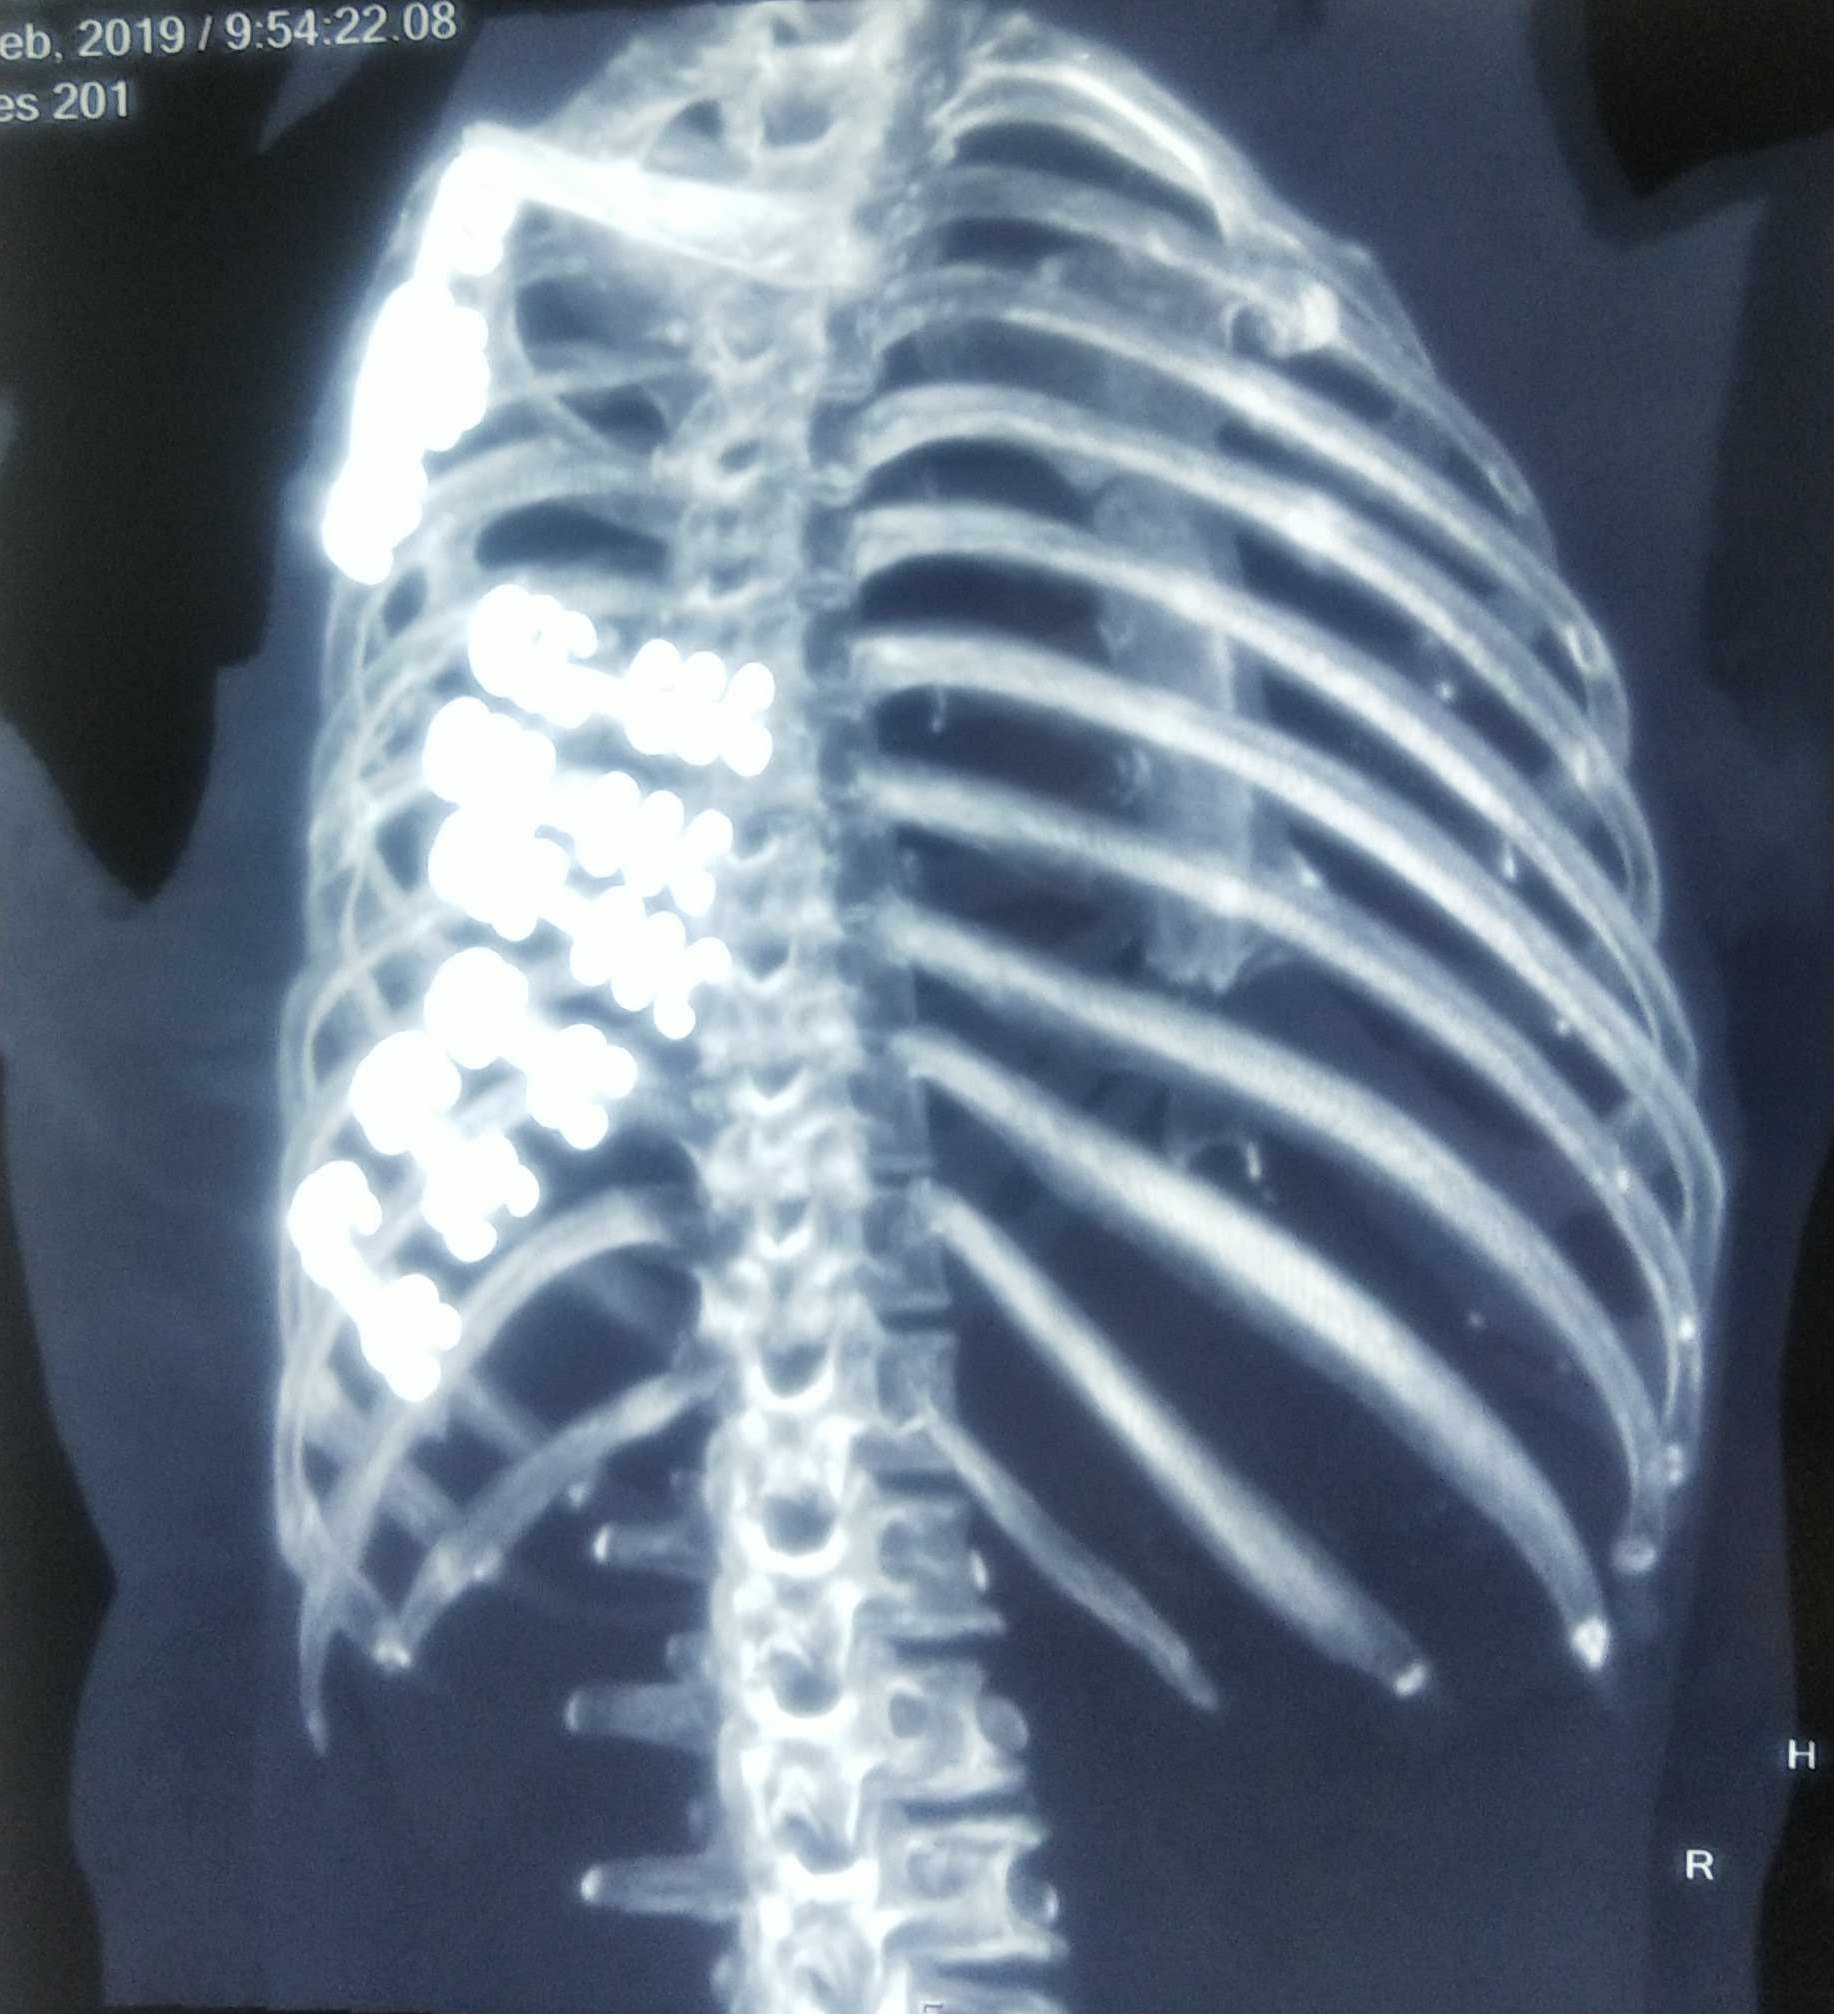

来院時 Ct a 左多第 3 11肋骨骨折を認め 第 9 11肋骨は 2 カ所で骨折していた 矢印 Download Scientific Diagram

左边第9块肋骨的胸部x光破裂权利后部第6块肋骨和可能的破裂侧向方面库存图片 图片包括有左边第9块肋骨的胸部x光破裂权利后部第6块肋骨和可能的破裂侧向方面

胸部x 線骨折右後第6肋骨和左9肋骨可能骨折側側照片檔及更多人照片 Istock